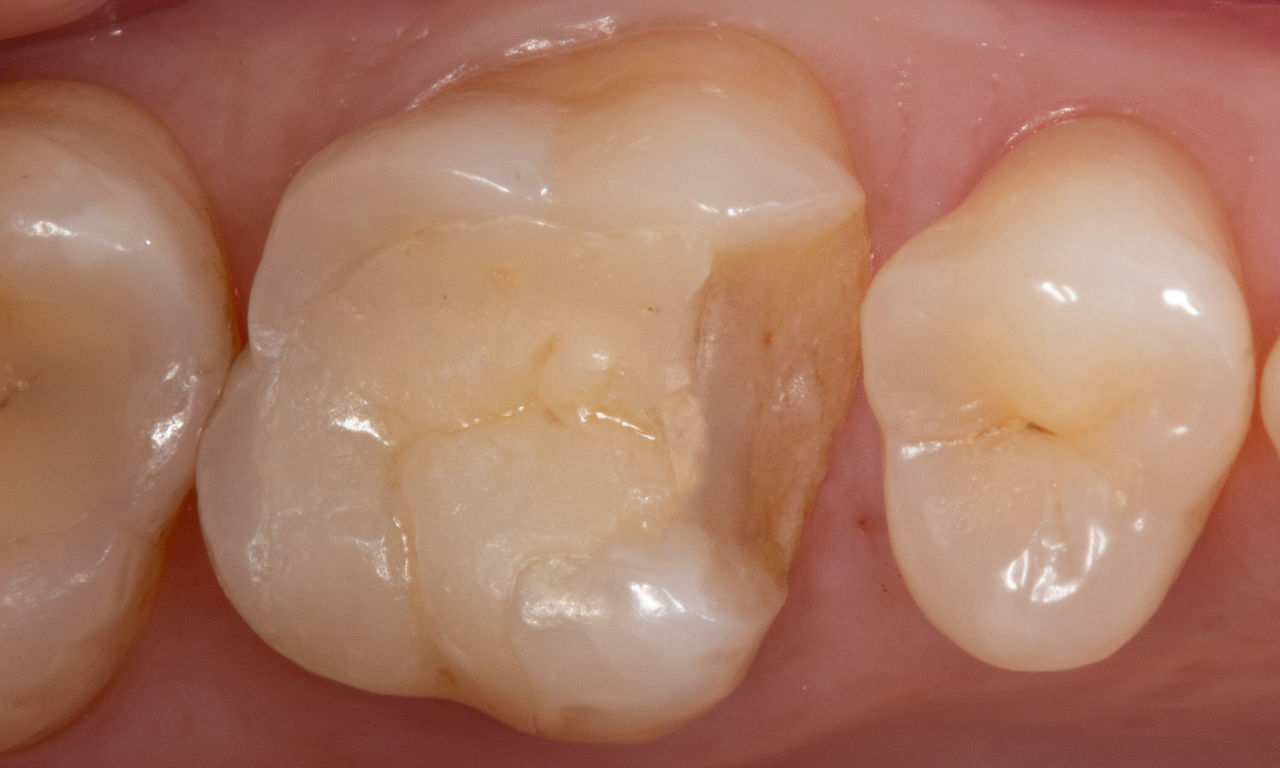

Lower second molar chairside restoration

A partial CEREC Tessera crown

A lower second molar with sensitivity presented with cracks as well as an extensive Class I composite restoration on the buccal surface. According to the minimally invasive concept a CAD/CAM partial crown was planned, fabricated and bonded using CEREC Tessera in a single visit.

Before: Failed amalgam restoration needing replacement. Patient complaining of sensitivity and tooth presenting multiple cracks.

After: Chairside CAD/CAM partial crown restoration fabricated with CEREC Tessera Advanced Lithium-Disilicate glass ceramic.

Dr. Carlos Eduardo Sabrosa

Rio de Janeiro, Brasil